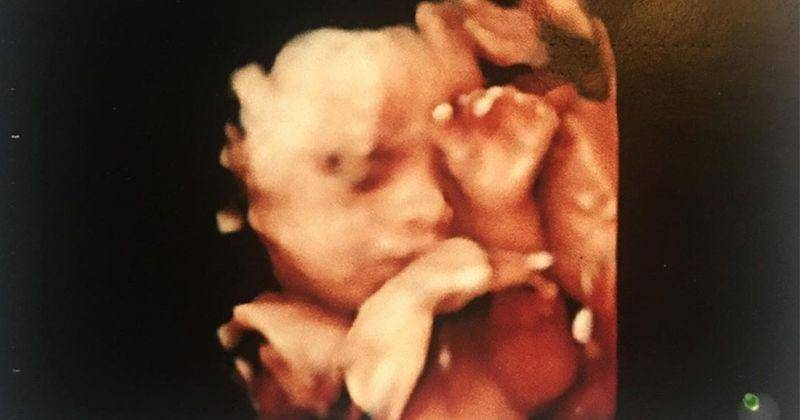

My whole entire world is living inside of me. Mama cant wait to see you. Bismillah #27weekspregnant

Seperti yang ia tuliskan dalam foto hasil USG, usia kandungan Ariska sudah memasuki trimester ketiga sekitar 27 minggu.